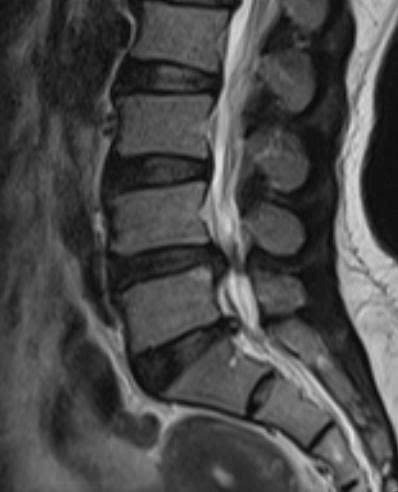

Khi đến khám và thực hiện chụp MRI cột sống thắt lưng tại Bệnh viện A, các bác sĩ Khoa Ngoại Chấn thương chẩn đoán bệnh nhân T. bị thoát vị đĩa đệm L4-5, L5-S1 và có chỉ định nhập viện phẫu thuật nội soi cột sống hai cổng để lấy nhân đệm, giải phóng chèn ép thần kinh.

Hình ảnh chụp MRI cột sống thắt lưng bị thoát vị đĩa đệm L4-5, L5-S1 của bệnh nhân T.